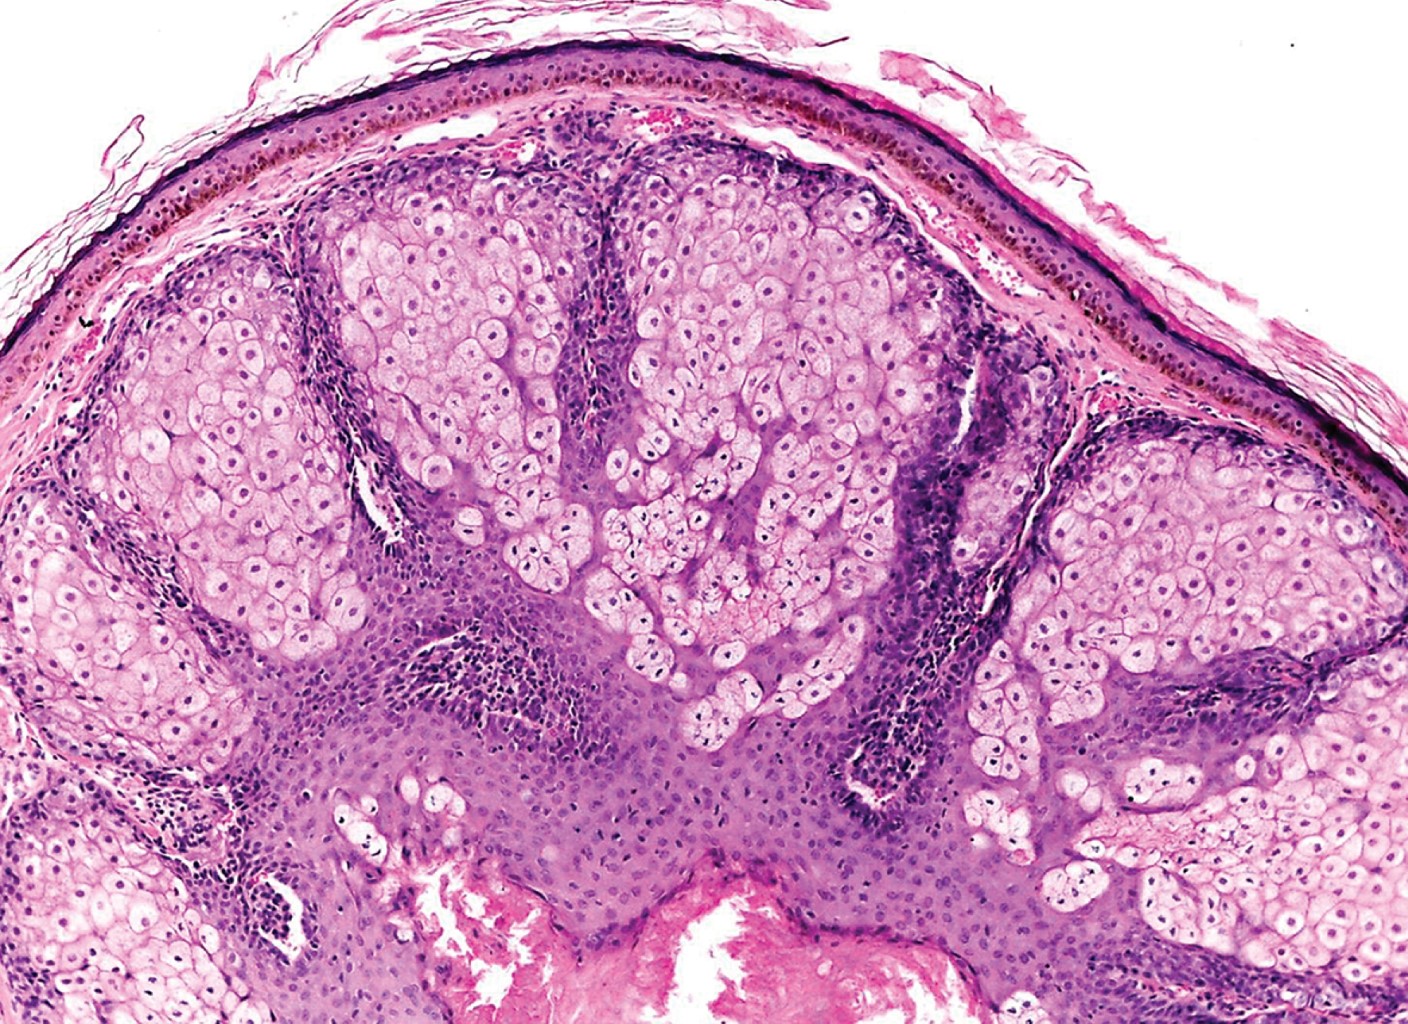

Paciente del sexo masculino de 11 años de edad, sin antecedentes familiares ni personales relevantes, quien acude por presentar dermatosis localizada a párpado superior derecho; constituida por una neoformación hemiesférica del orden de 0.5 cm, de color amarillo-rosado, de bordes bien definidos, con telangiectasias en su superficie, de aspecto lobulado (Figura 1). Con 10 años de evolución, asintomático. Sin tratamiento previo. Con la impresión clínica de tumor de anexos se realizó biopsia escisional, cuyo reporte histopatológico demostró la presencia de una neoformación exofítica, en cuya dermis se observaban cordones epiteliales constituidos principalmente por células sebáceas de características normales, las cuales en algunas zonas se encontraban delimitadas por dos o tres hileras de células basaloides. Con los hallazgos anteriores se realiza el diagnóstico histopatológico de adenoma sebáceo (Figuras 2 y 3).

El estudio histopatológico muestra una neoformación bien circunscrita ubicada en zonas intermedias de la dermis, separada por tabiques de tejido conectivo. Está constituida por lóbulos sebáceos inmaduros, los cuales son irregulares en tamaño y forma. En los lóbulos están presentes dos tipos de células: en la periferia se observan células basaloides indiferenciadas, las cuales son idénticas a las de las glándulas sebáceas normales, y sebocitos maduros en el centro.6

En la periferia se puede apreciar un número variable de capas de pequeñas células germinativas con núcleos vesiculares redondos u ovalados y escaso citoplasma. Este mayor número de células basaloides o germinativas permite hacer el diagnóstico diferencial con la hiperplasia sebácea, la cual contiene en su estructura máximo dos capas de dichas células. Éstas se entremezclan con las células sebáceas maduras de ubicación más central (que son mucho más grandes y tienen citoplasma espumoso, pálido y núcleos hipercromáticos centrales).

En ocasiones se observa una empalizada periférica. Algunos lóbulos muestran degeneración quística, y otros parecen conectarse directamente con el epitelio superficial. Más de la mitad del lóbulo en el adenoma sebáceo está compuesta por células sebáceas maduras. En algunas ocasiones se observan adenomas sebáceos gigantes que muestran aumento de la actividad mitótica en el componente de células basaloides, lo cual no debe interpretarse como probable signo de malignidad.